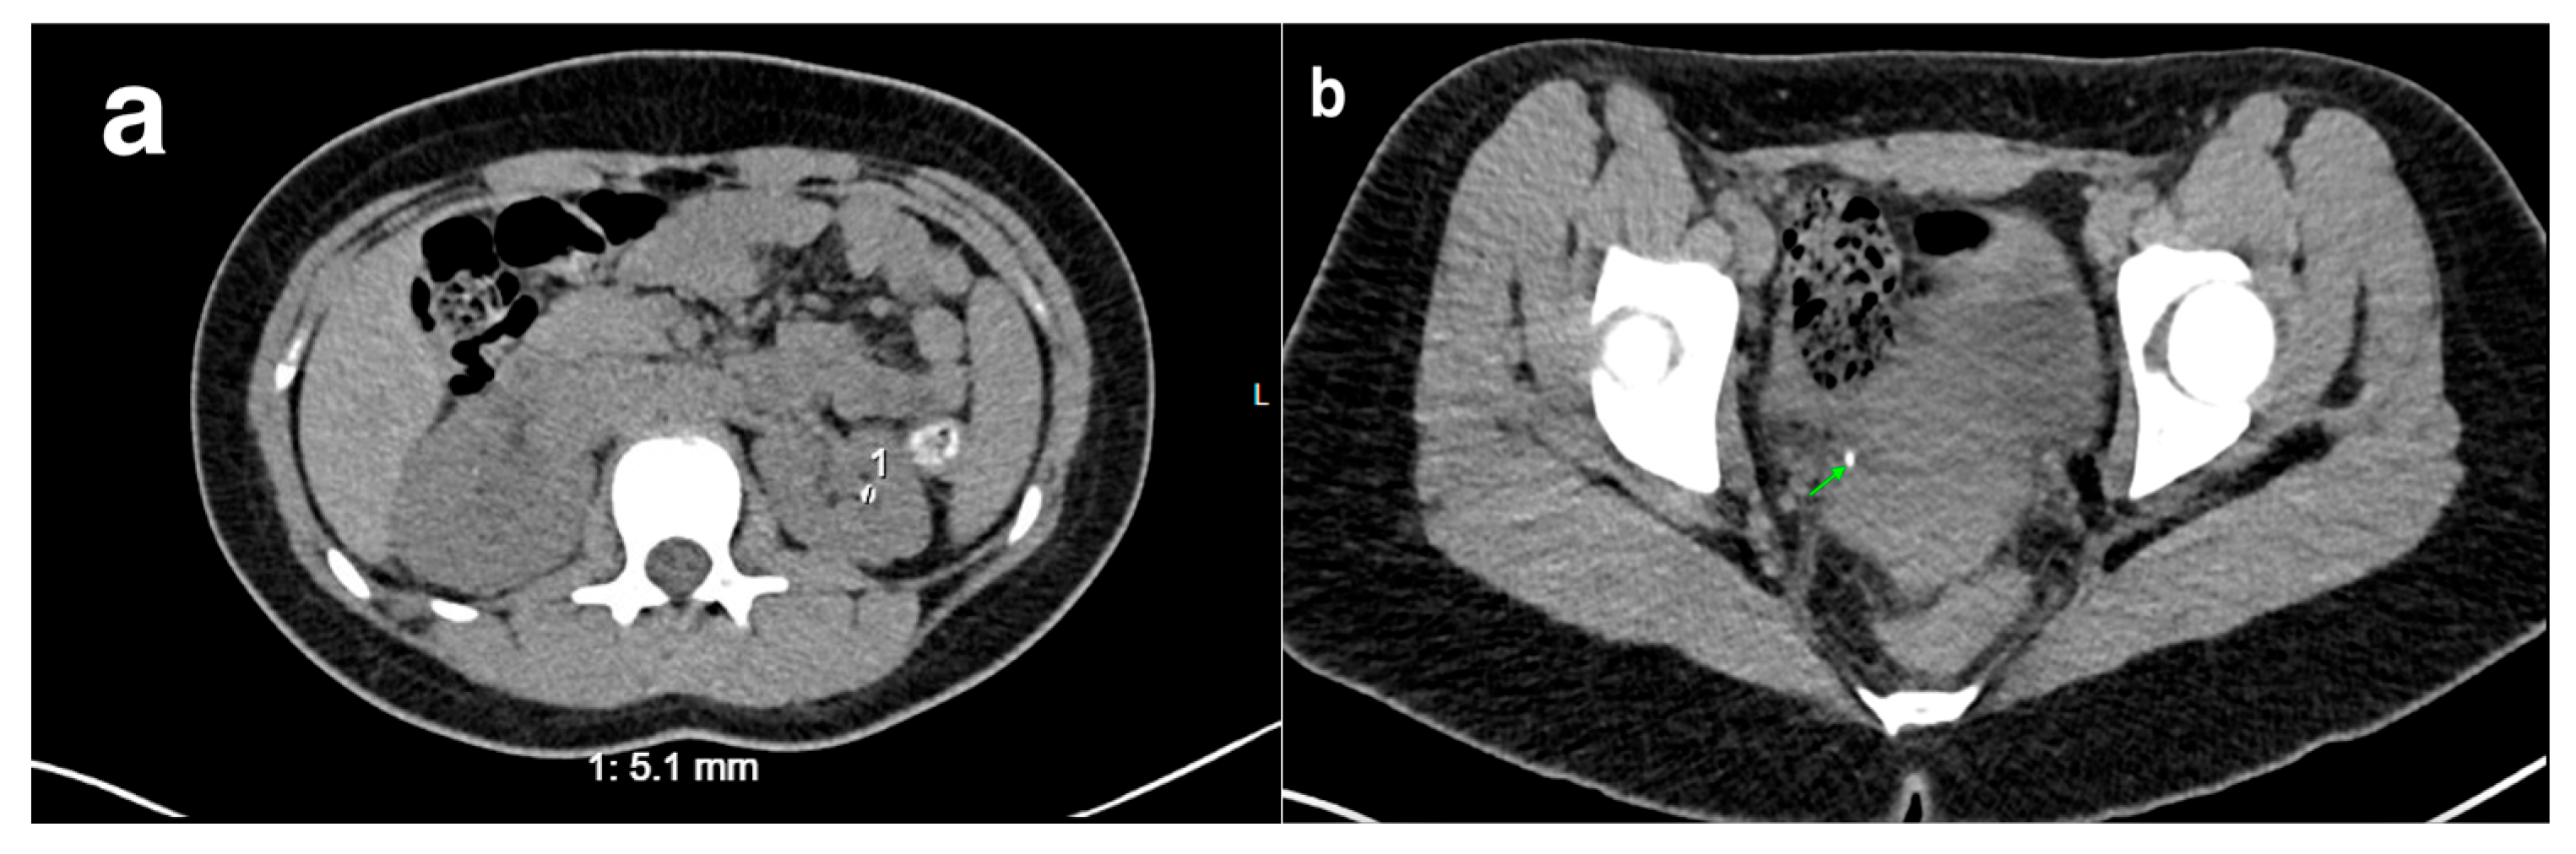

Figure 7. A CT scan of a 15-year-old female with a history of recurrent pyelonephritis shows a scarred and atrophic right kidney (indicated by green arrow).

DMSA scanning is the gold standard for diagnosing acute pyelonephritis, as clinical criteria alone are not always reliable [42,43]. While US may show renal enlargement and poor corticomedullary differentiation, it is less sensitive and specific compared to other imaging modalities. MRI and CT offer good sensitivity (Figure 6), but DMSA remains preferred.

20. Nephrolithiasis